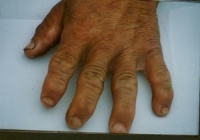

⑴关节增粗:最多见的是多发性、对称性指间关节增粗,常先出现在第二、三、四指的第一指间关节。一般右手指关节增粗比左手明显,受机械损伤的关节或妇女带顶针的指关节增粗较重。

本病病情发进展以后,除关节疼痛等早期表现继续加重外,主要有以下症状体征出现:⑴、关节增粗:最多见的是多发性、对称性指间关节增粗,常先出现在第二、三、四指的第一指间关节。一般右手指关节增粗比左手明显,受机械损伤的关节或妇女带顶针的指关节增粗较重。

⑹、短指(趾)畸形:指节发育比常人短,手小形方。或因各指(趾)发育障碍程度不同,其长短失去正常互相间的比例关系。

⑺、短肢畸形,身材矮小:各管状骨发育障碍程度常不均等。有的病人桡骨早期生长停止,尺骨相对较长,尺骨茎突向下主背侧移位,手向桡侧倾斜,造成巴德隆畸形。发病年龄小而病变重者可形成大骨节病性侏儒,病人肢体与头及躯干不成比例,一般上臂明显短于前臂,小腿明显短于大腿,躯干接近正常人。